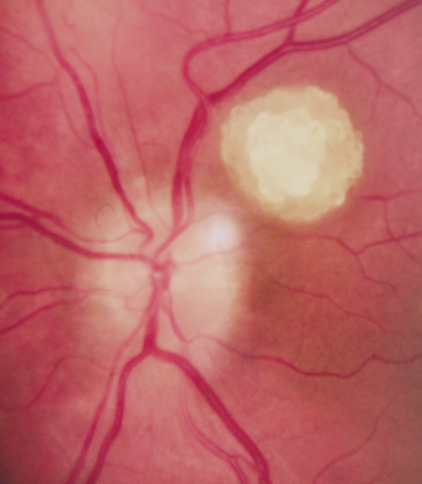

Although in Van der Hoeve's original description the term phakoma or phakomata was a generic term for the tumors occurring in various organ systems,1 it has become associated with the retinal astrocytic tumors of TSC,3 which occur in about 50% of affected patients and are bilateral in 25% to 30% (Table 3, Fig. 16).154,156

Fig. 16. Tuberous Sclerosis Complex: astrocytic retinal hamartoma, also referred to as retinal phakoma. There are three types: translucent type (a), calcified, nodular or “mulberry” type (b), and intermediate type (c).156 These usually do not affect vision and require no treatment. About half of patients are affected and there are bilateral lesions in 25% to 30%.154–156

Type 1. In the most common type, relatively flat, smooth-surfaced, and translucent lesions often difficult to see (an abnormal light reflex may be the only clue). They are in the posterior pole, superficial to the retinal vessels.156

Type 2. Raised, calcified, multinodular (“mulberry-like”) tumors in the posterior pole (80% within 2 disk diameters of the optic nerve).156

Type 3. The least common, intermediate type shows features of types 1 and 2, often in the posterior pole.156

Historically, the presence of mixed (type 3) hamartomas led to the suggestion of evolution from the type 1 to the type 2.157 A long-term photographic study found that although the types remained unchanged, a minority of types 1 and 3 increased in calcification and a new lesion was noted that had not been evident on an earlier photograph.157 All three types of retinal hamartomas may be found in young children. There is no correlation between age and the predominant type of lesion.156

Histologically, phakomata are composed of glial astrocytes—elongated, fibrous astrocytes with small oval nuclei, arising from the retina or the optic disc. The type 2 lesions contain basophilic, calcified drusen-like deposits within a dense vascular network. On fluorescein angiography, the type 2 lesions show autofluorescence, leakage with transit of dye, and marked late hyperflorescence.3,113

Astrocytic retinal hamartomas usually do not affect vision and require no treatment. Vitreous seeding and vitreous hemorrhage have been reported in association with phakomata, but these are rare.158,159 Laser photocoagulation may be considered in rare cases were exudation induces serous retinal detachments.160 The differential diagnosis of “white retinal lesions” includes retinoblastoma, toxoplasmosis and toxocara.3,113